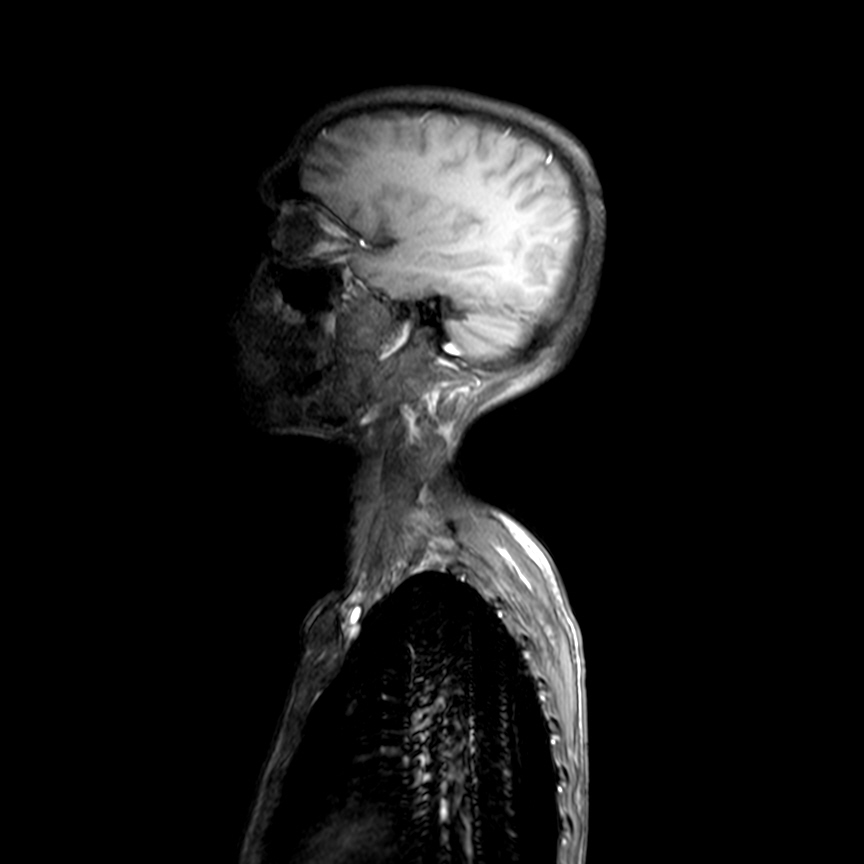

A 35 year old man with sudden quadriparesis 3 months back found to be due to cervical spinal tuberculosis, decompressed neuro-surgically with minimal improvement of power but still bed ridden. What is intriguing is a peculiar diaphragmatic involuntary movement reflected in his abdominal muscles.

Radiological images: